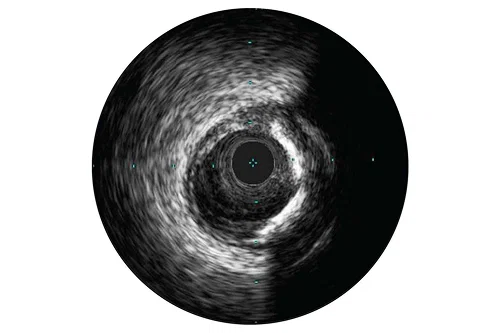

Assessment of lesions

IVUS can help clarify the degree and type of stenosis (i.e, MLA, plaque burden, and calcium). While IVUS can also characterize plaque rupture, thrombus, and dissection, calcium may be more common in everyday PCI. Calcium is an important factor in your stenting strategy. It is characterized by very bright areas with acoustic shadowing and /or reverberations that may indicate calcium is present.